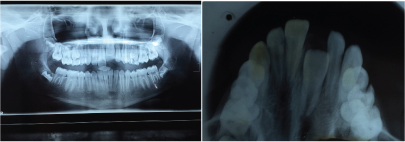

A 12-year-old female patient reported to the Department of Orthodontics of Maulana Azad Institute of Dental Sciences, New Delhi with chief complaint of missing upper front tooth. On clinical examination it was found that maxillary left central incisor (21) was missing [Table/Fig-1]. No significant history of trauma or premature/delayed shedding of primary left central incisor was reported. Panoramic and maxillary occlusal view revealed impacted left central incisor with dilacerated root [Table/Fig-2,3]. Since the contralateral central incisor had erupted fully in the mouth and the root formation of the impacted central incisor was almost complete, it was decided to disimpact the tooth (21). Disimpaction was planned by surgical exposure followed by elastic traction with the help of removable appliance. Since the patient had well aligned upper and lower arches in good occlusion, it was decided to use a modified removable appliance for extrusion of 21. A removable appliance with modified labial bow was fabricated. Labial bow in the anterior region was fabricated with 22 gauge wire and helices were incorporated in the labial bow adjacent to left central incisor region. Retention was provided by the acrylic coverage in the palatal region and by well formed retentive clasps. Surgical exposure of left central incisor was performed by open exposure technique. A bondable button was placed onto the labial surface of exposed left central incisor crown [Table/Fig-4]. Patient was trained to use elastic in triangular fashion to engage button on 21, and two helices of the labial bow, which resulted in an extrusive force of 20 grams for disimpaction of 21[Table/Fig-5] [1]. Patient was advised to change the elastic daily and was reviewed every three weeks. At the end of six months, complete disimpaction of 21 was achieved with the tooth in its optimal alignment into the upper dental arch and in good relation with lower teeth [Table/Fig-6,7]. Post disimpaction panoramic view reveals tooth 21 in the optimal position with respect to maxillary occlusal plane [Table/Fig-8].

Pretreatment panoramic and maxillary occlusal view showing vertically impacted maxillary left central Incisor with dilacerated root.